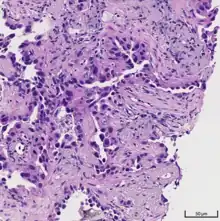

Acinar pattern.[16]

Solid pattern.[17]

• acinar predominant [19]

Cell patterns identifying subtypes are associated with prognosis, ranging from favorable (lepidic) to intermediate (acinar and papillary) to poor (micropapillary and solid).[2]

Adenocarcinoma of the lung tends to stain mucin positive as it is derived from the mucus-producing glands of the lungs. Similar to other adenocarcinoma, if this tumor is well differentiated (low grade) it will resemble the normal glandular structure. Poorly differentiated adenocarcinoma will not resemble the normal glands (high grade) and will be detected by seeing that they stain positive for mucin (which the glands produce). Adenocarcinoma can also be distinguished by staining for TTF-1, a cell marker for adenocarcinoma.[29]

As discussed previously, the category of adenocarcinoma includes are range of subtypes, and any one tumor tends to be heterogeneous in composition. Several major subtypes are currently recognized by the World Health Organization (WHO)[1] and the International Association for the Study of Lung Cancer (IASLC) / American Thoracic Society (ATS) / European Respiratory Society (ERS):[30][31][32] lepidic predominant adenocarcinoma, acinar predominant adenocarcinoma, papillary predominant adenocarcinoma, micropapillary predominant adenocarcinoma, solid predominant adenocarcinoma, and solid predominant with mucin production. In as many as 80% of these tumors, components of more than one subtype will be recognized. Surgically resected tumors should be classified by comprehensive histological subtyping, describing patterns of involvement in increments of 5%. The predominant histologic subtype is then used to classify the tumor overall.[2] The predominant subtype is prognostic for survival after complete resection.[33]